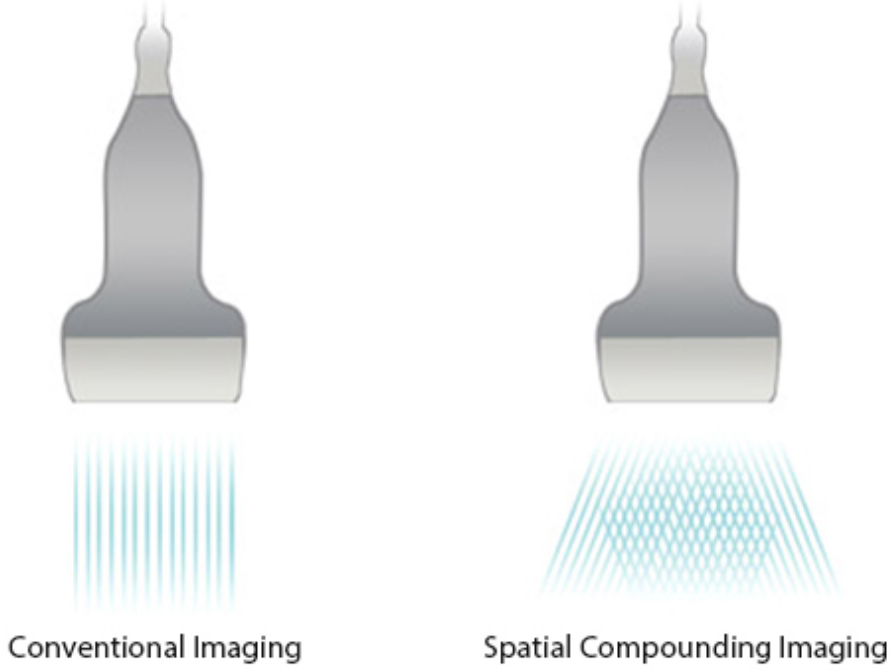

PSH?(??? ??? ??)

??? ??? ??? ???? ?? ??? ?? ?? ??? ??? ?????.

iBeam?

?? ?? ?? ??? ???? ?? ??? ??? ? ?? ?? ???? ???? ???? ???? ? ????.